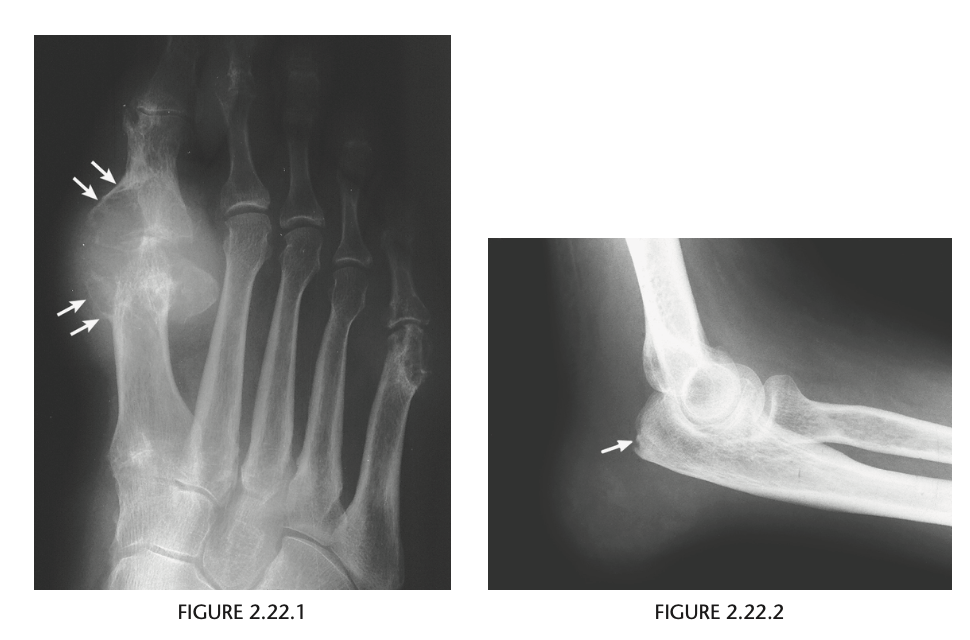

Anteroposterior view of the right foot

of the first patient shows soft-tissue swelling, ex-

tensive periarticular erosions with sclerotic borders,

overhanging edges in the first metatarsophalan-

geal joint, and preservation of the articular space

(Fig. 2.22.1, arrows). A lateral view of the right el-

bow in a different patient reveals marked soft-tissue

swelling and a faint radiopacity in the region of

the olecranon bursa. Minimal erosive changes are

present in the posterior surface of the olecranon

(Fig. 2.22.2, arrow).

Gout

The most common findings are punched-

out erosions with sclerotic borders and overhanging

cortical margins, referred to as overhanging edges or

margins. The erosions may be intraarticular, periar-

ticular, or located some distance from the joint. Soft-

tissue tophi, producing masses adjacent to the areas

of bony erosion, may occasionally contain faint

calcification within them. Generally, the articular

space is preserved, and periarticular osteopenia is

minimal. The olecranon bursa is the most common

site of gouty bursal involvement.